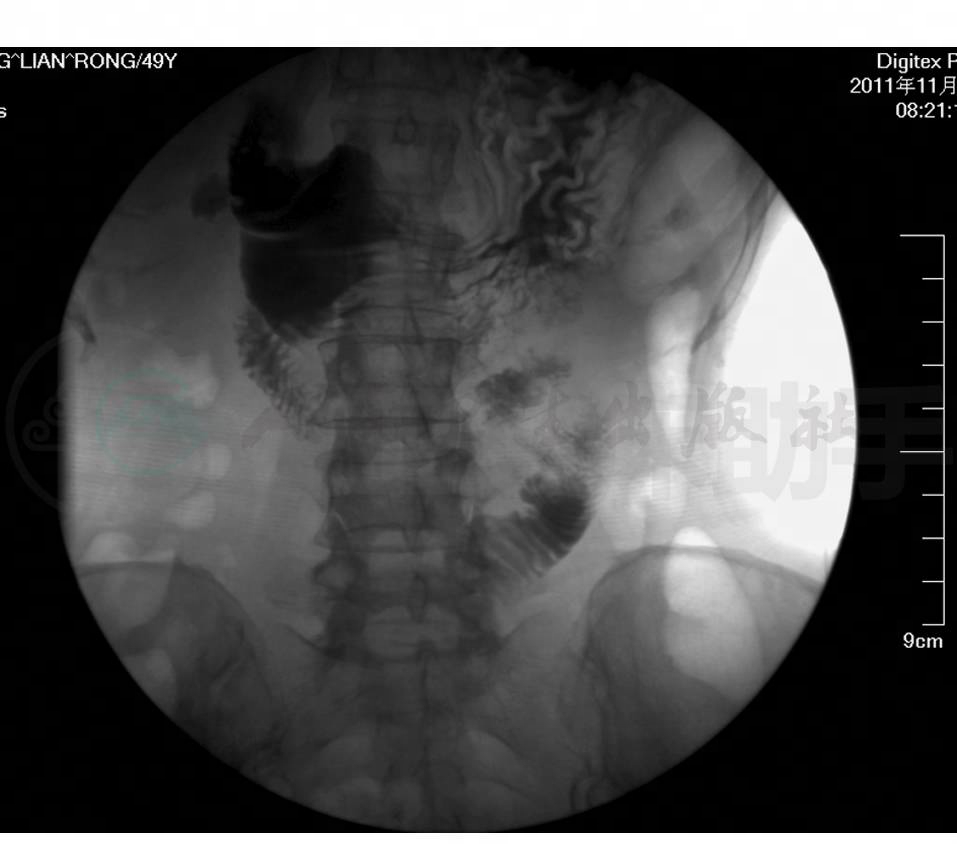

患者仍频繁恶心、呕吐胃内容物,伴上腹痛,不排气、排便。体格检查:腹软,中上腹、右下腹及中下腹有压痛,无反跳痛及肌紧张,肠鸣音约2次/分。立位腹平片:肠腔内见肠气影,可见小气液平,以下腹部显著。考虑患者仍存在消化道梗阻,给予禁食水、胃肠减压、生豆油经胃管注入后洗肠治疗。患者间断腹痛发作,给予山莨菪碱10mg肌注后腹痛可明显缓解。进一步完善全腹增强CT+血管三维重建,结果提示腹主动脉、门脉主干及其主要分支未见异常。完善全消化道泛影葡胺造影进一步寻找梗阻部位。口服泛影葡胺(76%泛影葡胺,100ml)造影:食管通过顺畅,黏膜规则。无力型胃,中等量潴留液,小弯侧最低点位于髂嵴连线下1cm,大弯侧最低点位于耻骨联合水平。胃壁蠕动减弱,黏膜连续规则。胃窦部胃小区稍模糊。十二指肠水平段可见纵行压迹(图1),近端肠管稍扩张,蠕动增强,造影剂通过压迹处困难,并可见多量逆向蠕动,且十二指肠内造影剂反流入胃。俯卧位时造影剂通过相对顺畅。上段小肠动力尚可,管腔未见扩张。考虑诊断为肠系膜上动脉压迫综合征。患者内科保守治疗效果不佳,转入外科行手术治疗(远端胃大部切除,结肠后十二指肠空肠吻合术,胃空肠ROUX-EN-Y吻合术)。术后病情恢复良好,进食后无上述症状发作。

图1 全消化道泛影葡胺造影

十二指肠水平段可见纵行压迹,近端肠管稍扩张